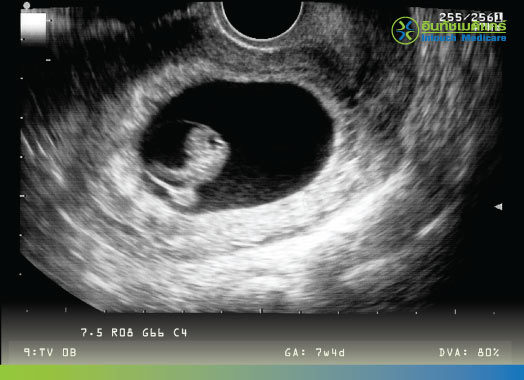

ตัวอย่างของภาพอัลตร้าซาวด์ อายุครรภ์ 7 สัปดาห์

เป็นการตรวจหาถุงการตั้งครรภ์ด้วยการใช้อัลตร้าซาวด์ (คลื่นเสียงความถี่สูง)

สามารถทำได้ 2 แบบ คือ การอัลตร้าซาวด์ผ่านหน้าท้องและผ่านช่องคลอด โดยการอัลตร้าซาวด์ผ่านช่องคลอดจะสามารถมองเห็นถุงการตั้งครรภ์ และโครงสร้างภายในได้ชัดกว่าการอัลตร้าซาวด์ผ่านหน้าท้องในผู้ที่อายุครรภ์น้อย

จะเริ่มมองเห็นถุงการตั้งครรภ์ได้ตั้งแต่อายุครรภ์ประมาณ 5 ถึง 6 สัปดาห์ (นับจากวันแรกของประจำเดือนรอบสุดท้าย)

จะเริ่มมองเห็นการทำงานของหัวใจของทารกในครรภ์ได้ตั้งแต่อายุครรภ์ 7 ถึง 8 สัปดาห์ (นับจากวันแรกของประจำเดือนรอบสุดท้าย)